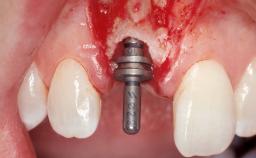

Immediate Flapless Placement of an Implant in a Maxillary Left Central Incisor Site

A 42-year-old female patient was referred to our clinic at the School of Dentistry of the University of São Paulo in November 2004, presenting a deficient restoration in the upper left central incisor. The clinical examination revealed no gingival retraction or any signs of gingival inflammation and, therefore, previous periodontal treatment was not considered. The patient presented a high lip line at full smile and a thin tissue biotype. This combination characterized a high-risk situation from an anatomic point of view, which required careful preoperative planning and cautious surgical execution.

| Placement Protocol | Immediate implant placement |

| Tooth Site | Maxillary incisor or canine |

| Socket Morphology | Single-root socket |

| Socket Integrity | Sufficient, with intact bone walls |

| Bone Volume | Sufficient, with intact walls |